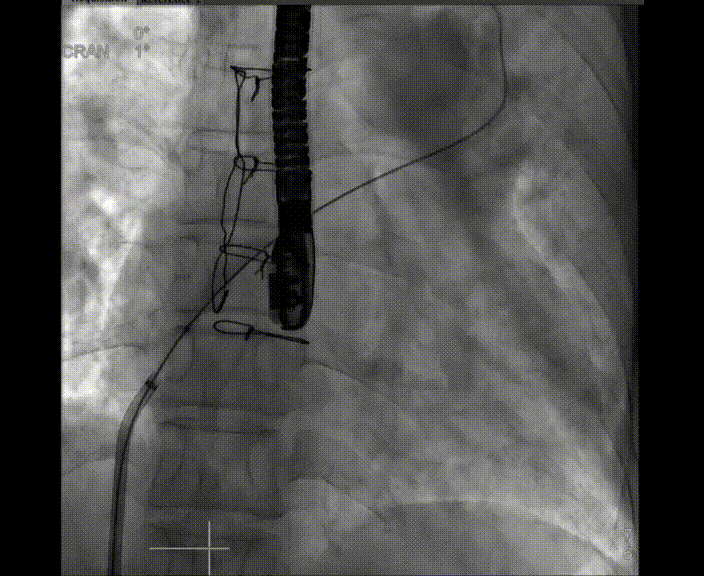

術(shù)中首先在局麻下穿刺股動(dòng)脈、股靜脈,完成心導(dǎo)管檢查評(píng)估后轉(zhuǎn)為全麻,在食道超聲引導(dǎo)下穿刺房間隔,穿刺成功后將加硬導(dǎo)絲送入左上肺靜脈建立軌道,根據(jù)患者病情行球囊預(yù)擴(kuò)張后植入6mm孔徑房間隔造孔支架,經(jīng)透視及食道超聲評(píng)估支架左右盤(pán)展開(kāi)良好,夾持于房間隔兩側(cè),固定穩(wěn)定、位置良好,食道彩超顯示房水平右向左為主分流,分流孔直徑符合預(yù)期大小,心導(dǎo)管檢查評(píng)估達(dá)到預(yù)期效果,釋放造孔支架。術(shù)后12h患者下床活動(dòng),恢復(fù)順利,擬于近日完善術(shù)后評(píng)估后出院。